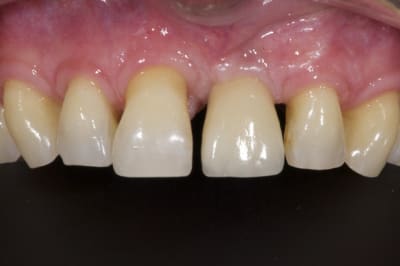

05/08/2014 à 11h23

Comme demandé en MP voici le contrôle 10 mois après la pose.

C'est acceptable je pense. Ce traitement a ses limite bien sûr mais peut être une indication voire une alternative dans certains cas spécifiques comme celui-ci.

Au passage, qui connait le nom que l'on donne à cette collerette de GA que l'on voit sur 13-12-11-22-23, j'ai oublié.

A omtjjz - Eugenol

1 zf3owi - Eugenol

Img 0812 mvp6i0 - Eugenol